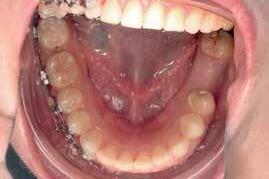

A 33 year old male presented to the orthodontic clinic referred by his prosthodontist . His main concern was the overeruption of maxillary right and left second molar due to bilateral loss of second and third mandibular molars that rendered the placement of prosthodontic implant and crown not possible. The patient had a 4 unit bridge, to replace missing maxillary right first and second premolar, with a root canal treatment and crown done on maxillary right lateral incisor and left second premolar. The patient’s main condition was to reduce the orthodontic system to a minimum with no visible appliances due to the nature of his work in sales.

Placement of temporary anchorage devices (Miniscrew) in the buccal and palatal side of the maxillary second molars in order to orthodontically intrude those teeth and create the required biological space for implant and crown placement in the mandibular posterior molar region(Figure 3).

Interproximal reduction in the area between maxillary first and second molar is necessary to allow the intrusion of the second molar without being hindered by the proximal contact of the first molar.(figure 4)

- 2 Buccal (1.6 mm diameter 8mm length) infra-zygomatic mini screw on upper 2nd molars of each side were placed this high in order not to interfere with the intrusive movement.

- 2 Palatal (1.8 mm diameter 8 mm length) placed in the midpalatal suture and another halfway the distance between the left second molar and the mid-palatal suture .

- The mini-screws were placed in a way that the resultant forces on each side are 120-150 g of force leading to close to pure intrusion of 2nd molars .